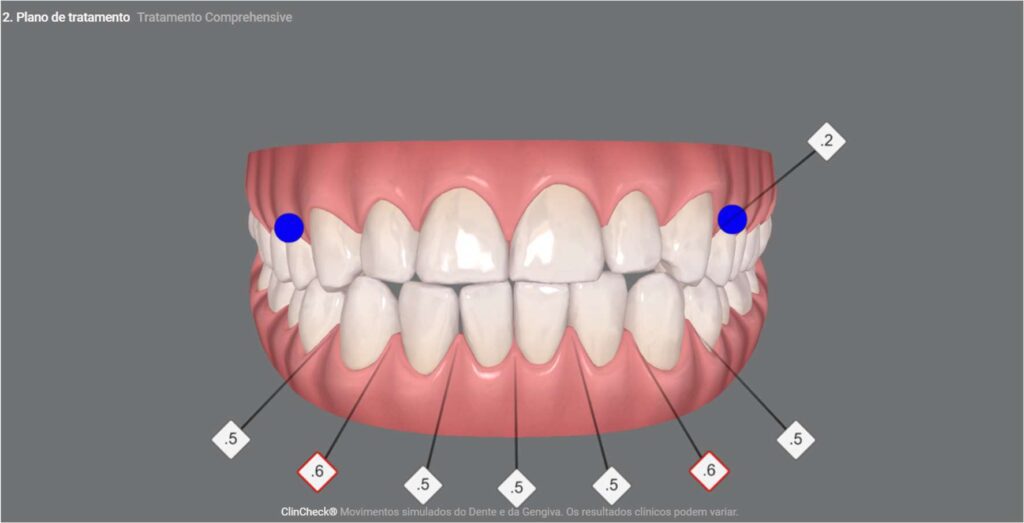

No primeiro ClinCheck deste paciente, apresentamos a fase inicial do planejamento, que visava o alinhamento, nivelamento e aprimoramento estético dos dentes anteriores. Se tivéssemos seguido apenas o que ele desejava, teríamos encerrado o processo ao final dos 20 alinhadores propostos nessa fase. No entanto, conscientes de que poderíamos oferecer mais, elaboramos o segundo ClinCheck para aprimorar ainda mais o tratamento, distribuindo melhor a carga mastigatória e aprimorando o encaixe da mordida, com mais 20 alinhadores.

Antes